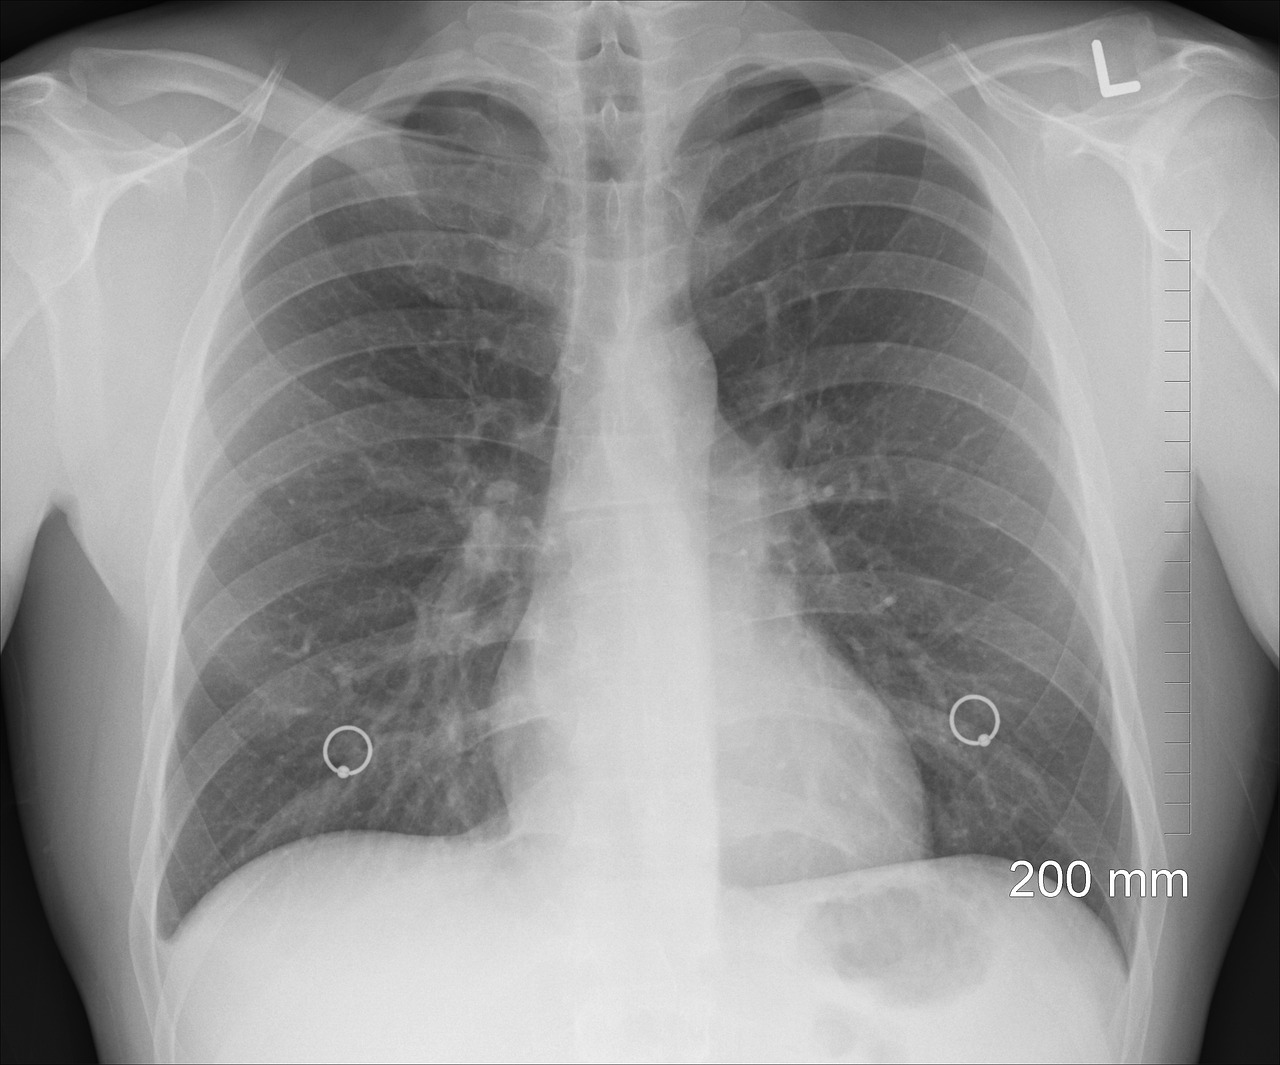

3) 영상 검사

단순 흉부 X-ray 검사로 폐부피의 증가, 횡경막 편평화 등의 소견을 확인할 수 있으며 CT 검사는 폐기종의 분포와 정도를 더 정확히 파악할 수 있습니다.